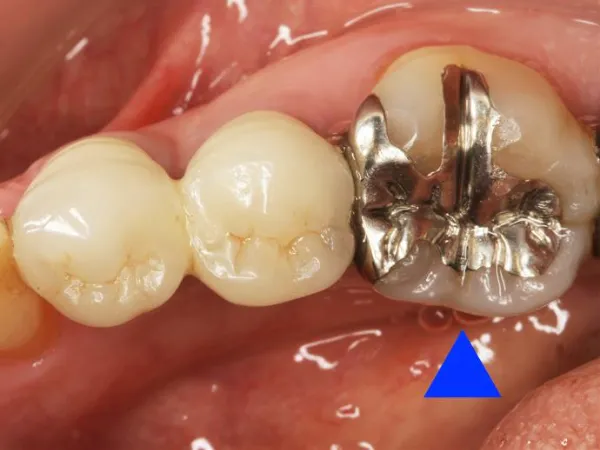

メタルインレー 金・銀・銅・パラジウム等からなる合金です。 | メリット ・天然歯よりも硬く丈夫 ・保険適用 デメリット ・銀色で審美性が低い ・金属アレルギーの原因になることがある ・長年使用することによりセメントが劣化する ・隙間からむし歯になる |